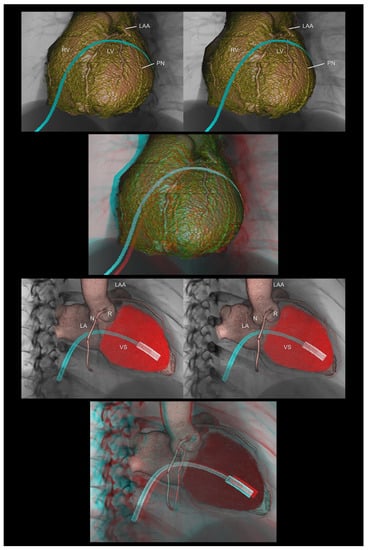

4.8. Virtual Procedural Simulation